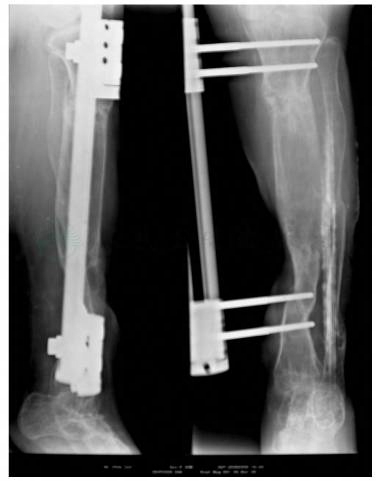

左胫腓骨正、侧位X线片(2004年6月14日):胫骨近段向外成角畸形,胫骨中、下交界处骨折线清晰,骨折线5cm以远的骨段向内侧移位约1/2直径。自胫骨近段成角畸形水平以远,胫骨力线正常。胫、腓骨及足部诸骨骨质密度普遍减低。踝关节处于跖屈18°位(图3、图4)。

图3 入院时X线片

图4 入院时下肢全长片